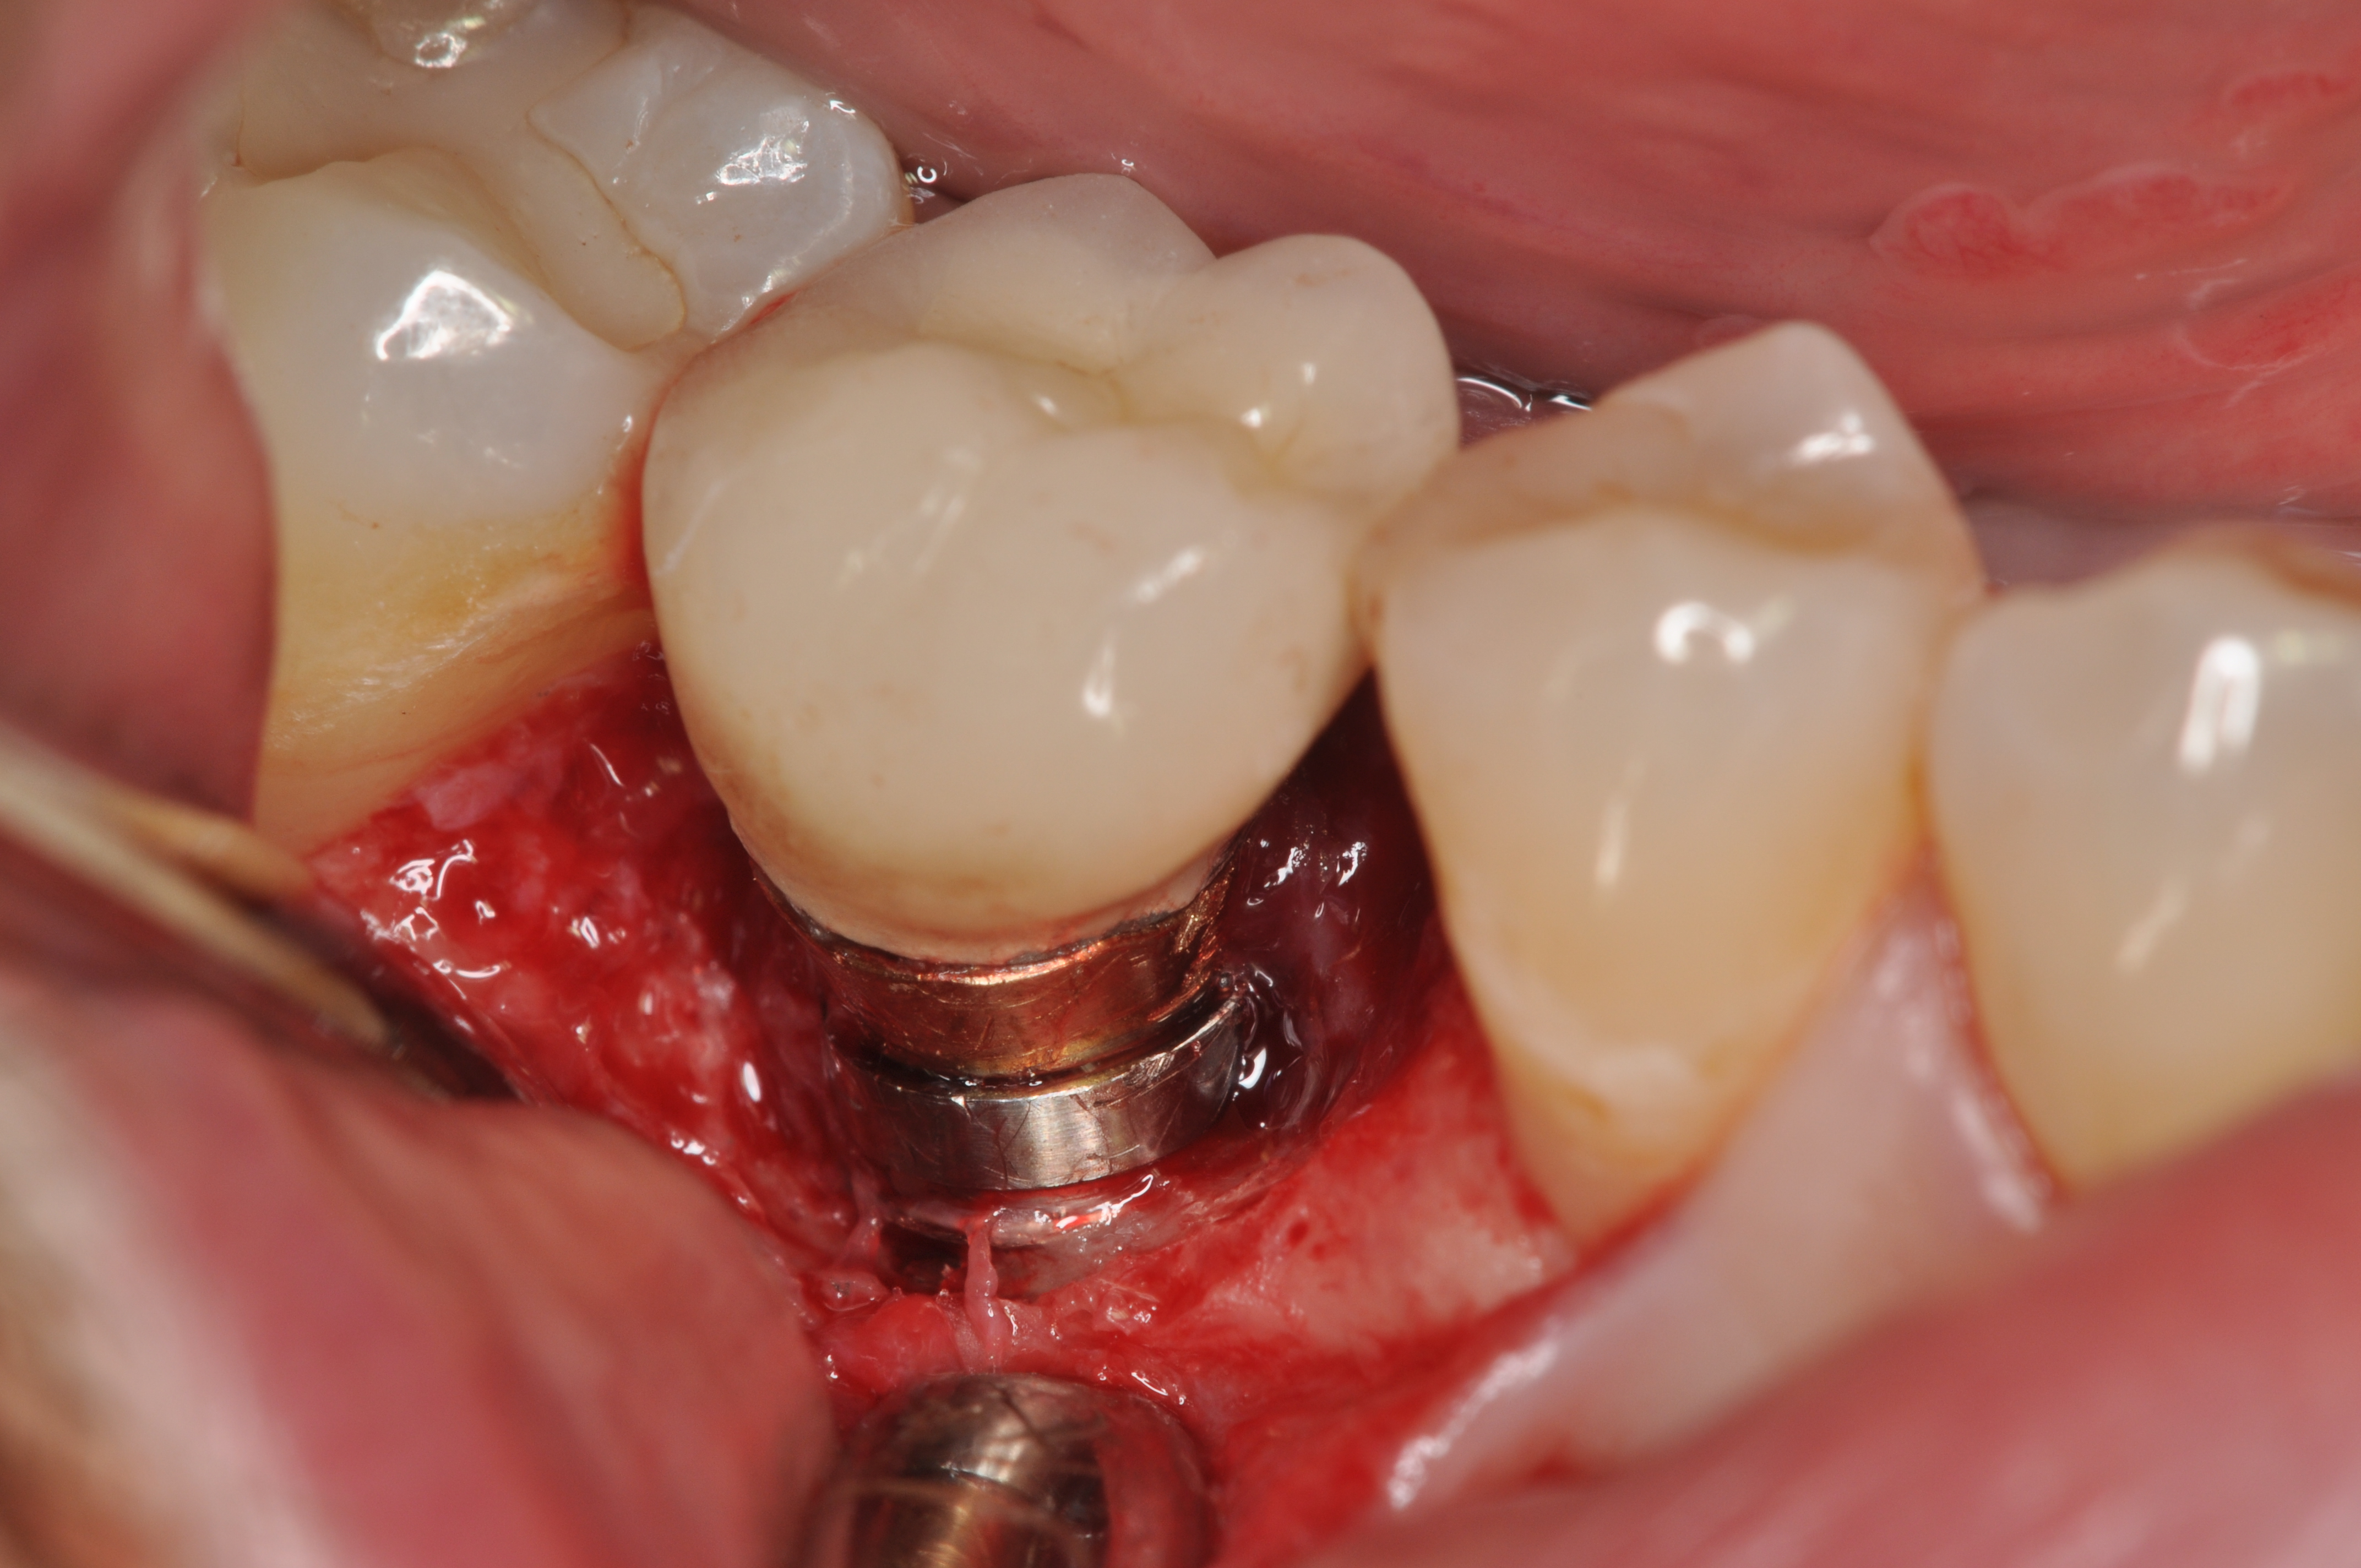

Fig 8. Loss of restoration and subsequent tissue overgrowth from broken abutment screw as shown in the radiograph (Fig 9).

Figure 8

Fig 9. Radiograph depicting fractured screw inside of the implant.

Figure 9

Fractured screws are challenging to retrieve, particularly when they are abutment screws. If the screw head is accessible, a hemostat can be used to remove it. However, when the screw breaks inside the implant (Figure 8 and Figure 9), removal can be highly complicated in order not to damage the implant’s internal threads. Therefore, many implant manufacturers have developed screw-retrieval kits. Because it is critical to be able to visualize the area, magnification using loupes and a surgical microscope may be necessary.8 Additional methods can be used to remove the fractured screw. A ¼ round bur set on a high speed can be used by lightly activating it, touching only the side of the screw. After repeating this technique several times, the screw may be able to be backed out with an explorer tip. Ultrasonic tips with copious irrigation may also dislodge the screw.7,20 In cases in which this fails, a small slot can be made in the head of the screw to back it out.21 If screw threads have been damaged during retrieval, they may be retapped using a tool obtained only from the implant manufacturer.7